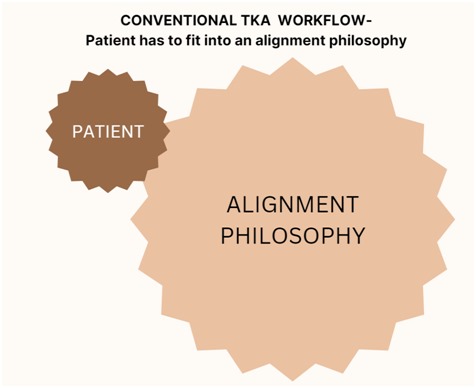

A knee replacement surgery is designed to provide pain free improvement in quality of life. The important determinant is alignment, ligament balance and good fixation of the implant. Since there is no one alignment that is superior to another the default standard has been “MECHANICAL NEUTRAL” approach where whatever the starting points- the aim is to get to a straight line. This approach potentially reduces the ultimate satisfaction rates

Robotic knee helps us to customize the alignment to the patient and not the patient to the alignment. The advantages of robotic knee is again Customization to patient needs, accuracy of the bone cuts, better ligament balancing and intraoperative immediate feedback for correction and modulation of the process for better outcomes.